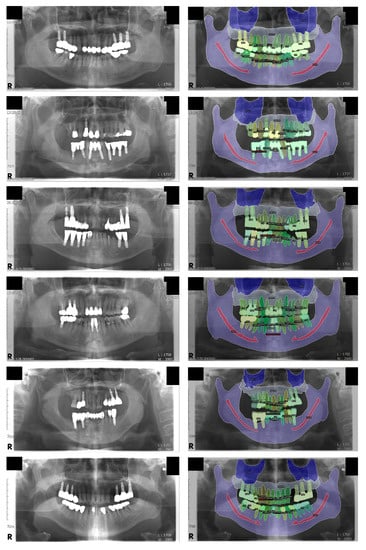

Finally, a total of 51 panoramic radiographs were randomly separated into 3 groups: training (n = 30), validation (n = 11), and test (n = 10) datasets. The age of the patients ranged from 32 to 79 years with a mean age of 60.6 years. Among the patients, 35 were male and 16 were female. The ground truths were annotated by a dental practitioner (J.-Y.C.), and an oral and maxillofacial radiologist (K.-H.H.) reviewed, corrected, and confirmed the annotations. Visualized examples of the annotations are shown in Figure 1.

Figure 1.

Visualized examples of the annotation results. A total of eight classes were used, including the background class. Four classes were assigned to semantic segmentation: maxillary sinus, maxilla, mandibular canal, and mandible. Three classes were assigned to instance segmentation: normal tooth, treated tooth, and dental implant.

For the panoptic segmentation task, the classes that are subjected to semantic segmentation are referred to as “stuff”, whereas those subjected to instance segmentation are referred to as “thing” [13]. The eight classes (five stuff and three things) included in the current study were as follows: maxilla, maxillary sinus, mandible, mandibular canal, normal tooth, treated tooth, dental implant, and unlabeled. Among these, normal tooth, treated tooth, and dental implant were assigned as things; thus, each object in these classes was segmented individually.

Some classes were categorized to help understand the results easily: the maxilla and mandible were categorized as “bone”, whereas the normal tooth, treated tooth, and dental implant were categorized as “tooth”. The maxillary sinus and mandibular canal were not categorized because they did not share a similar morphology with the other classes.